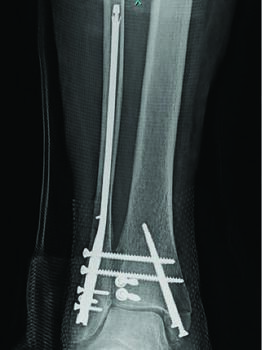

Recently, the literature described minimally invasive plate osteosynthesis (MIPO) for distal tibial fractures as an alternative option to Ilizarov external fixation, utilizing internal fixation with minimal incisions and minimal surgical trauma to soft tissues.4 Management of these distal tibial fractures with MIPO enables preservation of soft tissues and the remainder of the blood supply. A full discussion regarding distal tibial fracture fixation is much beyond the scope of this article, but typically fracture reduction/ fixation here is through either an anterolateral or medial incisional approach. Medially, one makes a straight incision at the level of the medial malleolus, taking care to preserve the saphenous vein and nerve. Fracture reduction is achievable through a multitude of options, including manual traction of the calcaneus, percutaneously placed reduction clamps, and temporary external fixation in a delta configuration. After reduction, one places a distal tibial locking plate through the medial malleolus incision in a subperiosteal manner. Plate screws are placed through this incision and additional locking screws are traditionally placed halfway up the plate, and at the proximal most portion of the plate through two separate small incisions. Recent studies call for an anterior curved incision that allows for visualization of the articular surface, as well as the medial malleolus and lateral most portion of the tibia for better reduction potential.5 This is the authors’ preferred method due to fracture visualization, plate-to-bone apposition, and operating efficiencies.

Pathways For Pilon Fractures With An Acute Hindfoot Nail

We have seen that acute hindfoot nailing for pilon fractures has become more common in orthopedic communities and academic centers alike, but only in specific high-risk patients with diabetes, end-stage renal disease, and the elderly. Typically, in this scenario, we typically minimally prep the joints are minimally prepped and keep incisions small to avoid wound complications associated with the above patient demographics. We then insert a retrograde compression nail traversing both subtalar and ankle joints which provides axial stability. Due to the load-sharing capabilities of the implant, we allow these patients to minimally weight-bear for transfers from the first postoperative appointment in a short leg cast. Studies show complication rates comparable with other methods of fixation and an eight percent major complication rate, but the literature is limited to level IV studies.6,7 Risks are obvious, and include, but are not limited to, hardware failure, nonunion, infection and amputation. The authors only use this on a limited basis for patients with uncontrolled diabetes mellitus, end-stage renal disease, severe vasculopathy, and/or advanced age.